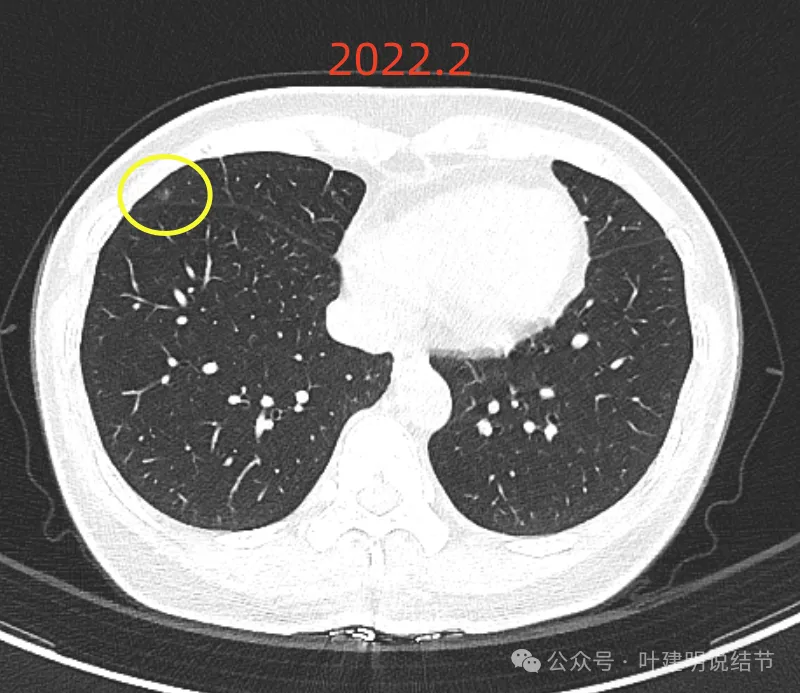

再看2022年5月时的影像:

这时B医院医生主张手术时的情况:

三处病灶均仍在,间隔3个月显然说不上明显进展或变化。这时候问诊我,我对比后认为风险仍低,能再随访,结友停掉了本已经预约的手术。